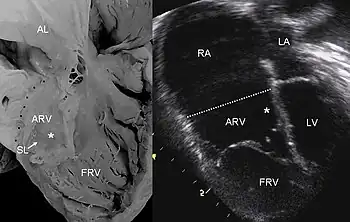

Pathological specimen and ultrasound image of a heart with Ebstein's anomaly: Abbreviations: RA: right atrium; ARV: atrialized right ventricle; FRV: functional right ventricle; AL: anterior leaflet; SL: septal leaflet; LA: left atrium; LV: left ventricle; asterisk: grade II tethering of the tricuspid septal leaflet

The annulus of the valve is still in the normal position. The valve leaflets, however, are to a varying degree, attached to the walls and septum of the right ventricle. A subsequent "atrialization" of a portion of the morphologic right ventricle (which is then contiguous with the right atrium) is seen. This causes the right atrium to be large and the anatomic right ventricle to be small in size.

Typically, anatomic abnormalities of the tricuspid valve exist, with enlargement of the anterior leaflet of the valve. The other leaflets are described as being plastered to the endocardium. Tethering the underlying ventricular wall is the most common for the posterior and septal leaflets, and sail-like anterior leaflets may be tethered to the RV free wall also.